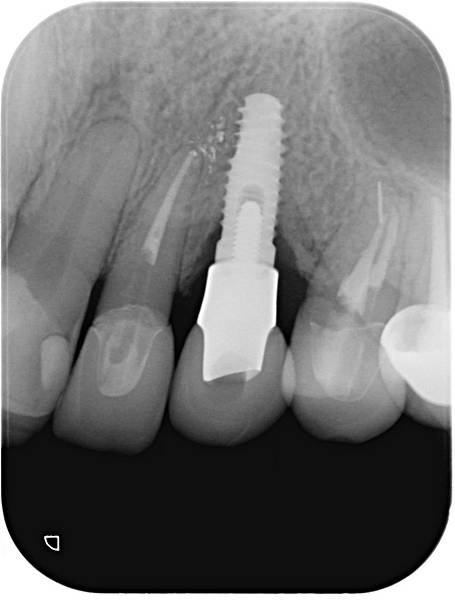

根尖片檢查.JPG

雖然我之前強調儘量不提植牙的部分,主要是網路上關於植牙的資訊實在太多了,但是最近又遇到一些真的很誇張的案例,在這裡分享主要是如果有類似的情況,請盡速就醫解決問題。